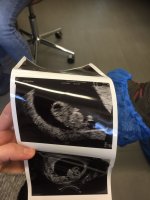

Her er mine bilder fra 9+1 og 12+1. Begge er tatt med innvendig ultralyd. Nederste er altså 9+1. Var også inne 9+6 pga en blødning, men da tok jeg ikke med meg bildene, syntes de var helt like som ved 9+1